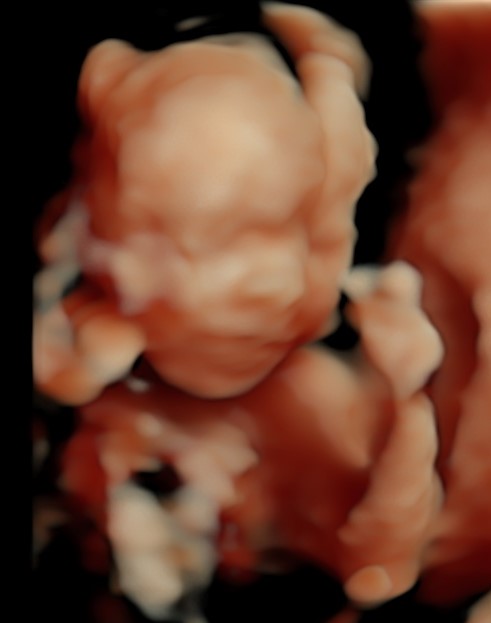

4D/5D/HD Ultrasound Gallery

Gallery